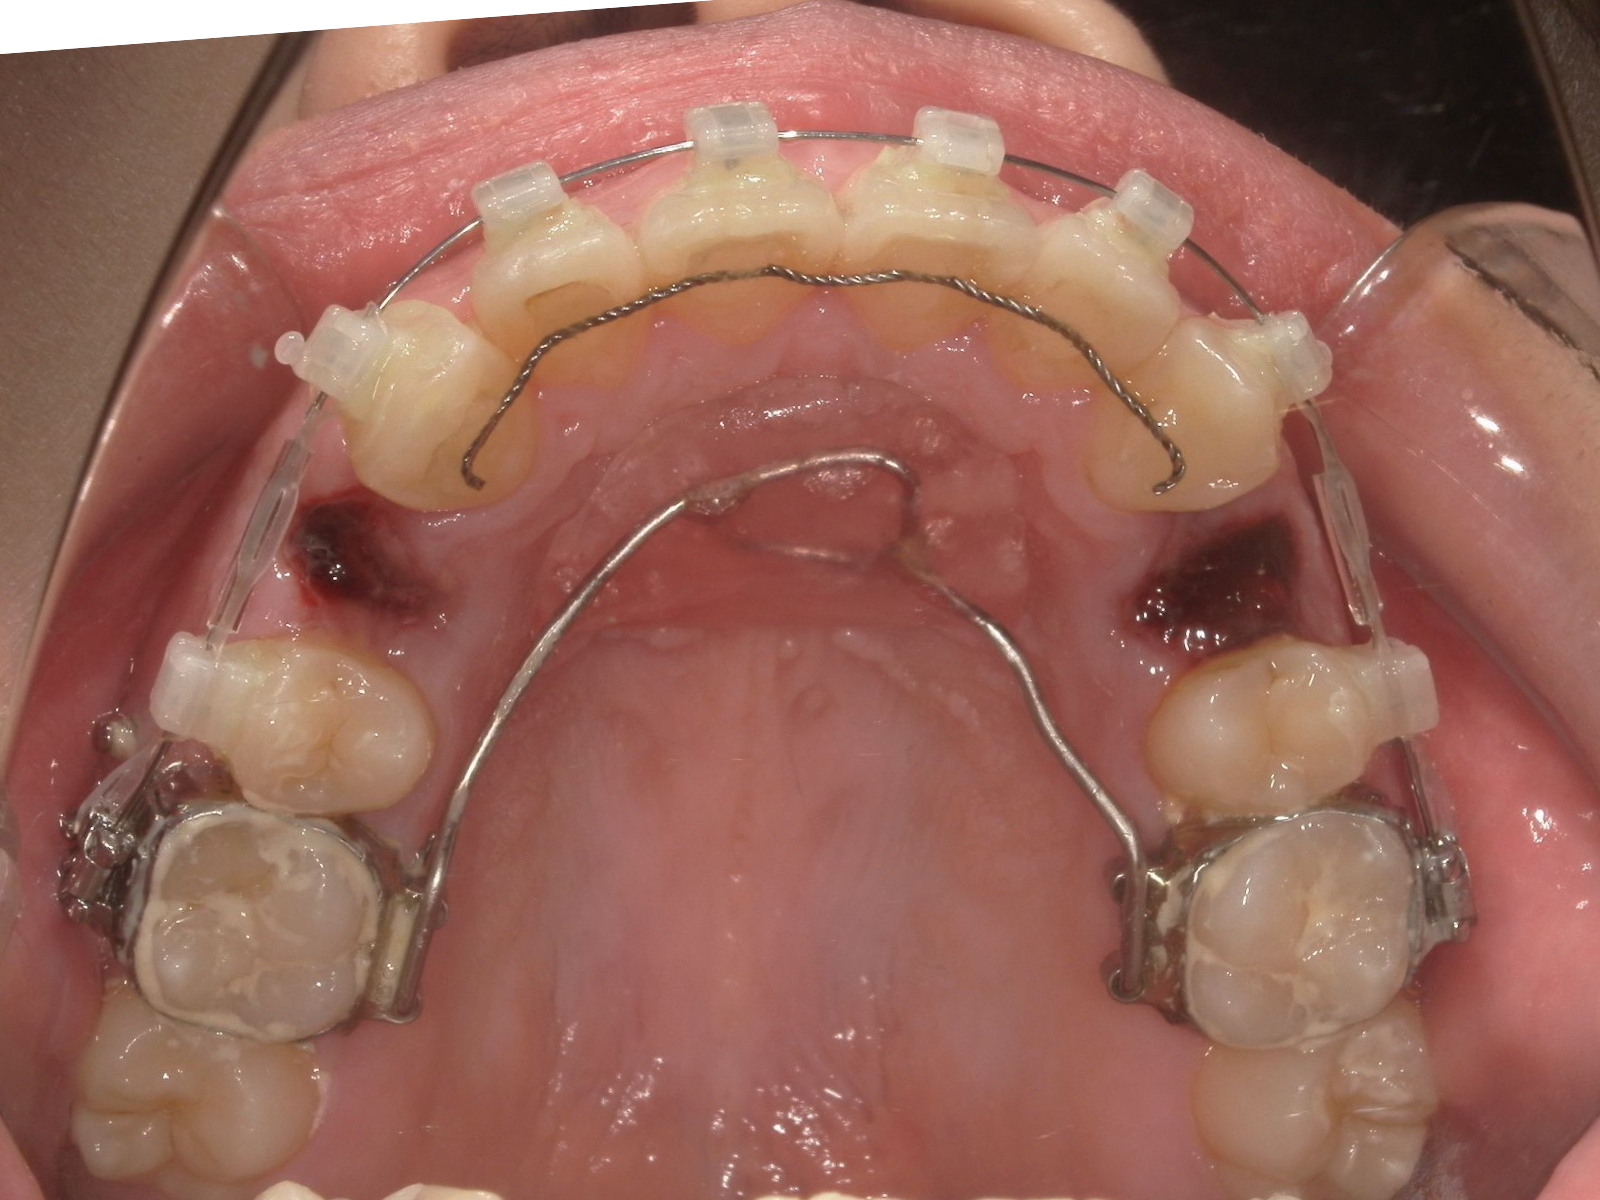

下の写真は、抜歯直後・6か月後・18か月後の経過写真です。

抜歯直後 口腔内(79-05a)|奈良の矯正歯科 治療開始 半年後 側貌+口腔内(79-05b)|奈良の矯正歯科 治療開始 1年半後 口腔内(79-05c)|奈良の矯正歯科